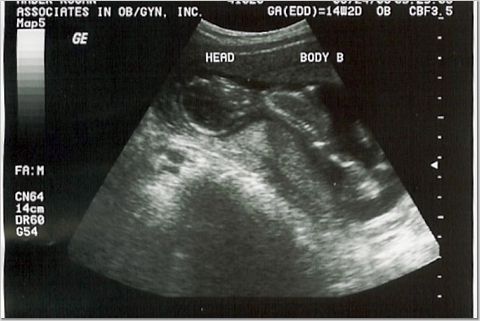

14 weeks - 3 ounces each

Heart rates 156 & 171 (heard them for the first time!)